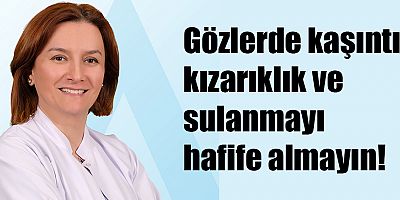

En sık görülen kanserler arasında yer alan akciğer kanserinin adını duymak bile insanı korkutmaya yetiyor. Dünyada her yıl 2 milyondan fazla, ülkemizde de 40 bin kişi, sigaranın en önemli risk faktörü olduğu ‘akciğer kanseri’ tanısı alıyor. Acıbadem Maslak Hastanesi Göğüs Cerrahisi Uzmanı Prof. Dr. Semih Halezeroğlu, kanserden kaynaklanan ölümler arasında ilk sırada yer alsa da, aslında tedavisinde atılan dev adımlar sayesinde erken evre akciğer kanserlerinin günümüzde yüksek başarı oranıyla tedavi edilebildiğine dikkat çekerek, “Erken evredeki akciğer kanserinin en yaygın ve ana tedavi yöntemini de cerrahi girişimle tümörün çıkarılması oluşturuyor. Günümüzde akciğer kanseri ameliyatlarının büyük bölümü, hastaya pek çok avantaj sunan kapalı ameliyatlarla gerçekleştiriliyor. Geliştirilen teknikler sayesinde erken evredeki akciğer kanseri ameliyatlarında yüzde 70’lere varan başarılı sonuçlar elde edilebiliyor ve hastalar uzun yıllar sağlıklı yaşamlarına devam edebiliyor.” diyor.

Tek Port VATS yöntemi: Pek çok fayda sağlıyor!

Akciğer kanserinin tedavisinde uygulanan kapalı ameliyatlardan son yıllarda en çok dikkat çeken yöntem ise tüm işlemlerin göğüs kafesinden yapılan tek bir küçük bir kesi ile gerçekleştirildiği Tek Port VATS yöntemi! Dünyada ve ülkemizde sayılı merkezlerde uygulanan yöntemin sağladığı en önemli avantaj; ameliyat sonrasında hastaların solunumunu çok rahat şekilde yapmalarına olanak sağlaması ve bağışıklığı düşürmediği için hastanın kanserle mücadelesinde başarı şansını artırması! Göğüs Cerrahisi Uzmanı Prof. Dr. Semih Halezeroğlu, bu yöntemin tanı ve tedavi işlemlerinin aynı operasyonda yapılmasına da imkan sağladığını belirterek, “Patoloji incelemesinde tümörün kötü huylu olduğu tespit edilirse aynı anda yapılan ameliyat ile kanserin tedavisi de gerçekleştiriliyor. Böylelikle akciğer kanserinin en erken şekilde teşhis ve tedavi edilmesine imkan tanıyor.” diyor.

Kapalı akciğer kanseri ameliyatları kendi içerisinde standart VATS yöntemi, robotik yöntem ve Tek Port VATS yöntemi olmak üzere 3 gruba ayrılıyor. Standart VATS ve robotik yöntemde işlemler göğüs boşluğuna 2 veya 3 yerden gerçekleştirilen kesiden girilerek yapılıyor. Göğüs Cerrahisi Uzmanı Prof. Dr. Semih Halezeroğlu, genel anestezi altında uygulanan Tek Port VATS yönteminde ise hastalığın olduğu göğüs boşluğu içerisine, sadece 2-3 cm arasındaki tek bir kesiden girildiğini belirterek, yöntemin nasıl uygulandığını şöyle anlatıyor: “Ardından 10 mm’lik bir cerrahi kamera hastalıklı olan bölgeye ilerletiliyor. Cerrah kamera aracılığıyla elde edilen görüntüleri ekranda görürken, operasyonu aynı kesiden ilerlettiği diğer cerrahi aletler ile gerçekleştiriyor. Hastalıklı kitle ‘endobag’ adı verilen cerrahi torba içerisine konularak göğüs boşluğu dışına çıkarıldıktan sonra operasyon tamamlanıyor.”

Göğüs cerrahisi ameliyatlarında daha az kesi yapılması hastanın sağlığı açısından son derece önem taşıyor. Göğüs boşluğu içerisinde hayati önemdeki kalp, akciğer ve büyük damarlar bulunduğu için bu bölge vücudun diğer bölgelerine göre çok daha geniş koruyucu sinir ağları ile örülüdür. Böylece bu hayati alanda oluşabilecek en küçük bir tehlikede ağrı oluşarak hasta koruma altına alınıyor. “İşte bu nedenle, göğüs bölgesinde ne kadar çok kesi yaparsanız o bölgedeki sinirlerde oluşacak hasar ve buna bağlı olarak ortaya çıkacak ağrı durumu da o oranda artıyor” diyen Göğüs Cerrahisi Uzmanı Prof. Dr. Semih Halezeroğlu, şöyle devam ediyor: “Ameliyat sonrası ağrının artması, hastaların normal nefes alıp vermelerinde güçlüğe, normal yaşama geçmelerinde gecikmeye ve bağışıklıklarında azalmaya sebep olabiliyor. Göğüs kafesinde yapılan ameliyatlarda işlemlerin tek bir küçük kesi ile gerçekleştirilmesi bu sorunların önüne geçerek hastaya birçok açıdan avantaj sağlıyor.”